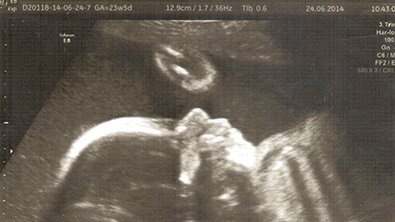

Беременность 23 недели 23 неделя беременности – это конец второго триместра, а значит, малыш уже подрос и полностью похож на миниатюрного ребенка. Все органы тела уже аккуратно сформированы. На ультразвуковом исследовании можно с легкостью увидеть ручки и ножки малыша. Лицо и уши четко прорисованы. Кора головного мозга постепенно развивается и готовится в жизни. Сердечко бьется четко, можно уже услышать 120-150 ударов в минуту. Легкие остаются слабыми, и не могут правильно функционировать вне утробы матери...